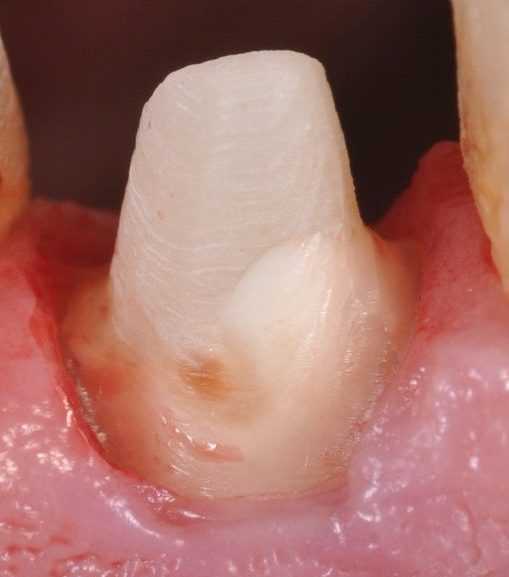

Сильное разрушение коронки — одна из причин для установки

(Рис.1)

(Рис.2)